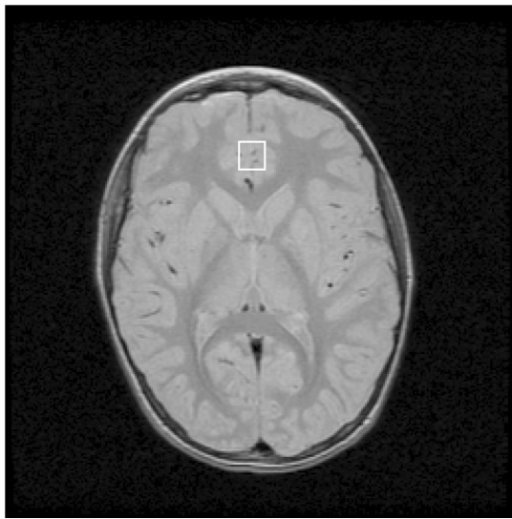

An image of a Magnetic Resonance Spectroscopy brain scan.

An image of a Magnetic Resonance Spectroscopy brain scan. Library of Medicine

To understand why Watanabe and his colleagues turned to Magnetic Resonance Spectroscopy (MRS). When it comes to brain scans, functional MRI or fMRI machines are better known. But fMRI machines measure brain function by tracking oxygen in the brain. Areas of the brain that are working hard use more oxygen, so it’s possible to connect brain function to oxygen usage. MRS machines, in contrast, track chemicals like carbon and nitrogen that are present in the brain’s neurotransmitters. They allow researchers to assess which neurotransmitters are present in the brain.

Using the MRS machine, researchers repeated the earlier experiments but with two changes. First, the two groups trained on either the usual (eight-block) condition, or the overlearning (sixteen-block) condition, but without a second training. And, before the first test and training researchers scanned the subjects’ brains in the MRS machine. Researchers also scanned the subjects’ brains 30 minutes after the training, and again 3.5 hours after the training. The post-test was again held on the second day.